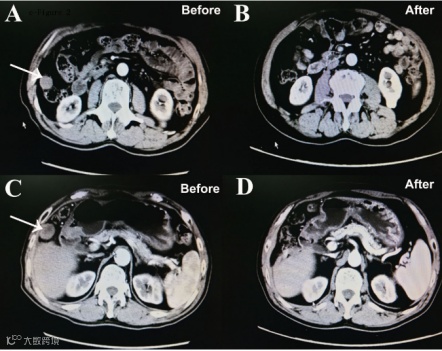

此次发布的研究是一项由上海东方肝胆外科医院程树群教授和石洁教授牵头的全国多中心、双盲、随机、安慰剂对照临床试验,纳入的患者均为晚期肝癌伴有远处转移,按1:1比例随机接受了全反式维甲酸联合FOLFOX4或者安慰剂联合FOLFOX4治疗。结果显示全反式维甲酸联合FOLFOX4治疗组的客观缓解率为24.5%,中位生存时间延长至16.2个月,显著高于安慰剂联合FOLFOX4治疗组的9.1%和10.7个月 (p值分别为0.031和0.025)。安全性分析结果显示两组不良反应发生率无统计学差异,证明了全反式维甲酸联合FOLFOX4是安全的。

靶向及免疫治疗是近年来晚期肝癌远处转移的首选方法,但是有效率低,大部分患者对靶向及免疫治疗不敏感。本研究的亚组分析显示,即使对于既往接受过靶向或免疫治疗的晚期肝癌远处转移患者,全反式维甲酸联合FOLFOX4治疗组仍显示出较好的疗效。文中还对全反式维甲酸联合FOLFOX4的疗效预测进行了蛋白组学分析,找到了化疗敏感(完全缓解或部分缓解)的标志物可供进一步研究。